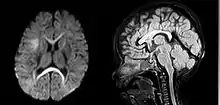

| An MRI of a patient with benign familial macrocephaly (male with head circumference > 60 cm) | |

Macrocephaly is a condition in which circumference of the human head is abnormally large.[1] It may be pathological or harmless, and can be a familial genetic characteristic. People diagnosed with macrocephaly will receive further medical tests to determine whether the syndrome is accompanied by particular disorders. Those with benign or familial macrocephaly are considered to have megalencephaly.

Benign macrocephaly can occur without reason or be inherited by one or both parents (in which it is considered benign familial macrocephaly and is considered megalencephaly form of macrocephaly). Diagnoses for familial macrocephaly is determined by measuring the head circumference of both parents and comparing it to the child's. Benign and familial macrocephaly is not associated with neurological disorders.[2] While benign and familial macrocephaly does not result in neurological disorders, neurodevelopment will still be assessed.

Although neurological disorders do not occur, temporary symptoms of benign and familial macrocephaly include: developmental delay, epilepsy, and mild hypotonia.[2]